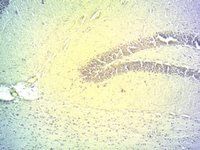

IHC-Fr analysis of PFA-fixed mouse hippocampus using GTX89019 DIO2 antibody, Internal.

Antigen retrieval : citrate buffer pH 4.5

Dilution : 2μg/ml